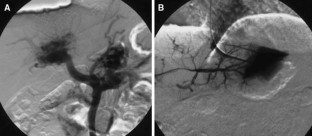

Case 1 was an 11-year-old boy diagnosed with rupture of the esophageal varices and hypersplenism due to congenital extrahepatic portal hypertension. Because of persistent hypersplenism and thrombocytopenia, he underwent meso-Rex bypassing with a left iliac vein graft interposed between the umbilical vein and the superior mesenteric vein. Case 2 was a neonate with a large hepatic tumor (mesenchymal hamartoma) that developed abdominal compartment syndrome at birth. The tumor was removed by right hepatectomy with excision of the portal vein bifurcation at 3 days of age. Porto-Rex bypassing was accomplished by end-to-end anastomosis between the portal vein trunk and the umbilical vein.

Sufficient hepatopetal portal flow through the umbilical vein was achieved in both patients and maintained for over 16 and 13 months, respectively. Although hypersplenism remained in Case 1, intrahepatic portal vein branches gradually widened and the cavernoma in the hepatic hilum disappeared within 2 months. Neither patient had symptoms or signs of portal hypertension at the most recent follow-up.